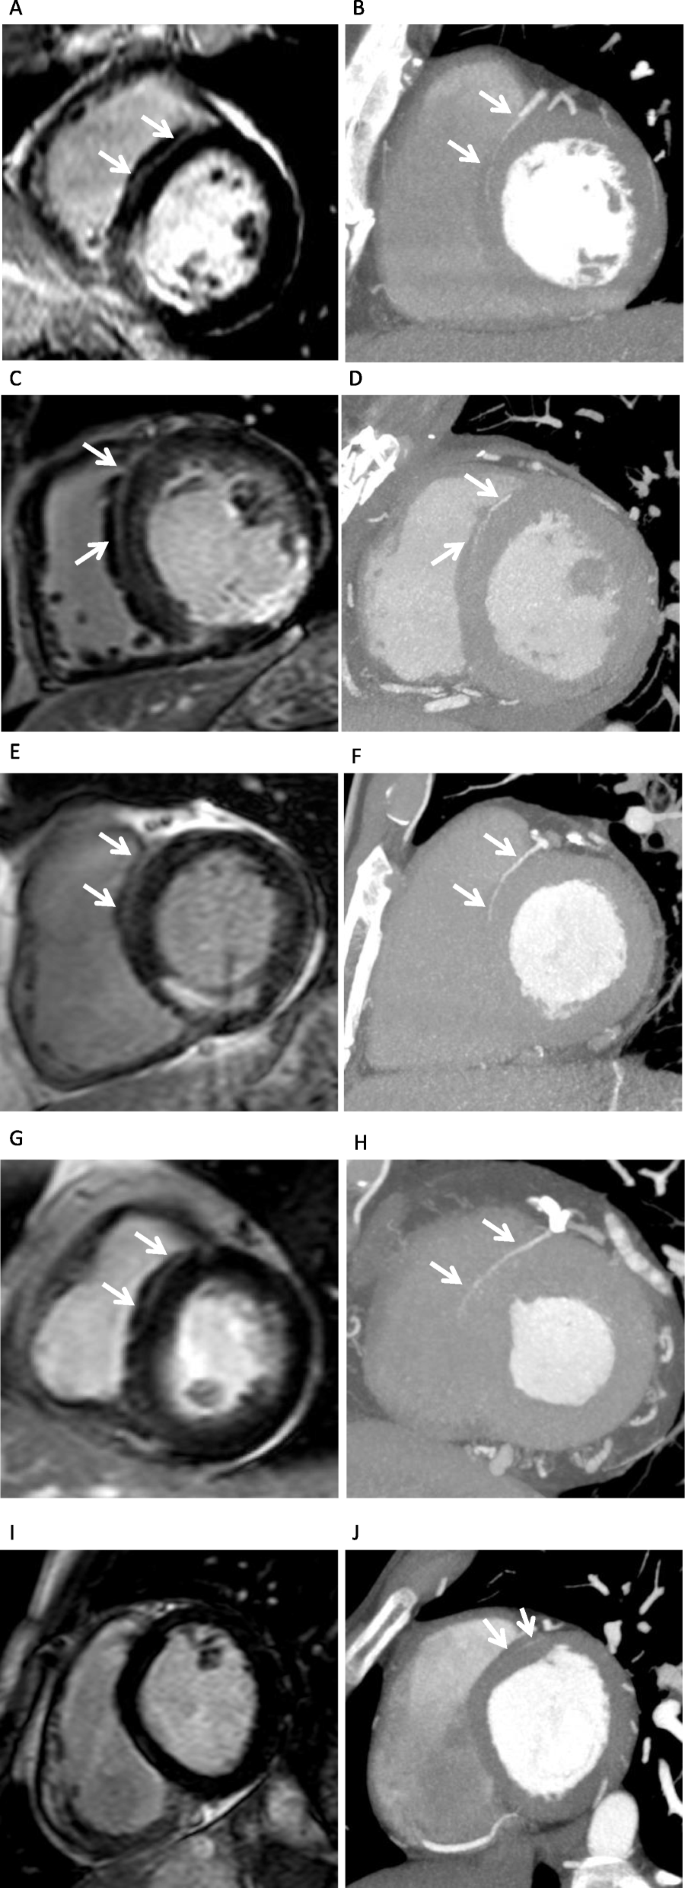

Among the 111 patients, there were 55 LHI+ and 56 LHI- patients. We observed that the LHI on LGE and anterior septal perforator arteries on CorCTA were very similar in shape and running direction (Fig. 3a-h). The measured length of the anterior septal perforator arteries on CorCTA was significantly longer than that in LHI on CMR LGE (16 ± 10 mm vs. 14 ± 10 mm; P < 0.05) (Fig. 3i, j). A linear regression analysis revealed that there was good agreement between LHI length on LGE and that of septal perforator arteries on CorCTA (R2 = 0.53, P = 0.13; Fig. 4). Among the 55 LHI+ patients, anterior septal perforator arteries were seen in the same region on CorCTA in 53 patients (96%) (Table 2). On the other hand, in the 56 LHI- patients, anterior septal perforator arteries were identified in only 39 patients on CorCTA (70%). The measured length of the anterior septal perforator arteries was significantly shorter in LHI- patients (10 ± 8 mm vs. 21 ± 8 mm for LHI+; P < 0.05) (Fig. 5).

a-j. Some patients of linear high intensity (LHI) in late gadolinium enhancement (LGE) cardiovascular magnetic resonance (CMR) and anterior septal perforator arteries in coronary computed tomography angiography (CorCTA). a-b. Fifty-six-year-old, male, acute inferior myocardial infarction. a LHI on CMR LGE, b anterior septal perforator arteries on CorCTA. C-D. Forty-eight years old, male, old inferior myocardial infarction. c LHI on CMR LGE, d anterior septal perforator arteries on CorCTA. E-F. Fifty-eight-year-old, male, old inferior myocardial infarction. e LHI on CMR LGE, f anterior septal perforator arteries on CorCTA. G-H. Seventy-one-year-old, female, acute anterior myocardial infarction. g LHI on CMR LGE, h anterior septal perforator arteries on CorCTA. i-j. LHI could not be identified (negative LHI) on LGE i. However, CorCTA could detect very thin anterior septal perforator arteries with higher spatial resolution j

In this study, LHI by CMR was visually confirmed as anterior septal perforator arteries on CorCTA in LHI+ patients. Since all LGE images were obtained using a 3D sequence, the septal high intensity could be identified well due to the high spatial resolution, high signal-to-noise ratio, and gapless slices. On the other hand, the measured length of the anterior septal perforator arteries on CorCTA was significantly longer than the LHI on CMR LGE. The reason may be that CorCTA has a higher spatial resolution than CMR, as shown in Fig. 3 (i) and (j), and could measure vessels to the periphery. In 56 of 111 patients, anterior septal perforator arteries were found on CorCTA, but these patients were defined as LHI- by CMR. Given that the mean length of the anterior septal perforator arteries on CorCTA was 10 ± 8 mm in LHI- patients, these arteries may not have reached the set LHI criteria (observable for 1.5 cm or more) in this study. It is possible that the LHI described here may be visualized increasingly with improvement in the spatial resolution and signal-to-noise ratio of CMR in future. Although in a small number (2 of 55 patients), for some patients that were defined as positive LHI by CMR, no marked anterior septal perforator arteries could be identified by CT. The LV myocardium includes not only the septal artery, but also vein, capillaries, arterio- and venoluminal vessels, and sinusoids, etc. [22]. Although very rare, these structures might also be recognized as LHI by LGE. However, we believe that the septal LHI is likely to be an artery, and not a vein, for the following reasons: first, it is very similar to the running of the septal perforator artery on CorCTA images; second, arteries with fast blood flow are considered to be more visible due to the CMR-inflow effect; third, LGE data is collected during diastole phase with emphasis on arteries. In this study, we could visualize a septal perforator artery using a slice thickness of 10 mm. First, a septal perforator artery is anatomically located along the short axis of the myocardium. Furthermore, by nullifying the myocardial signal using the IR sequences, it was possible to visualize the septal perforator artery running inside the myocardium at high signal and obtain high contrast. For these reasons, we considered that the septal perforator artery could be clearly depicted on the CMR short-axis slice, which has a lower spatial resolution than CorCTA.